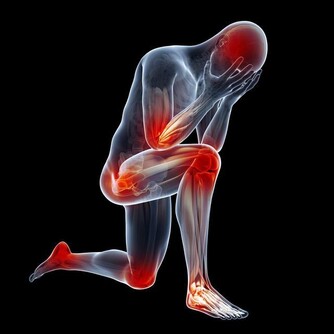

可如果我們的肝臟出現了病變,一開始我們並不能感受到明顯的疼痛。

如果肝臟到了疼痛難忍的時候,那就為時已晚了。

4、多多運動每天保持適量運動,並根據個人的肝功能的不同情況逐漸控制運動量。

運動初期,可在不影響身體舒適度的情形下慢跑,以疲勞度控制慢跑時間。